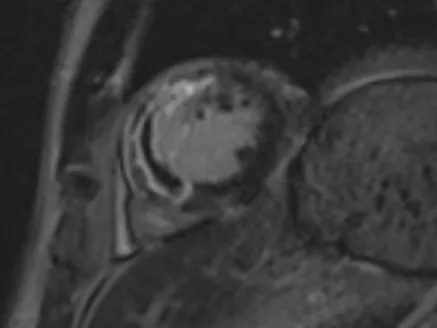

PCI术后即刻应用基于压力导丝的冠脉功能学全面评估解决方案(IMR/FFR等)进行全面评估,测得LAD IMR 46(+),FFR 0.87,提示存在CMD。心脏磁共振结果也提示存在微血管阻塞。

择期处理后侧支,并应用冠脉功能学全面评估解决方案(IMR/FFR等)进行左前降支IMR等的复查,测得LAD IMR 32(+),FFR 0.86,提示LAD仍存在CMD,但IMR值较前下降。